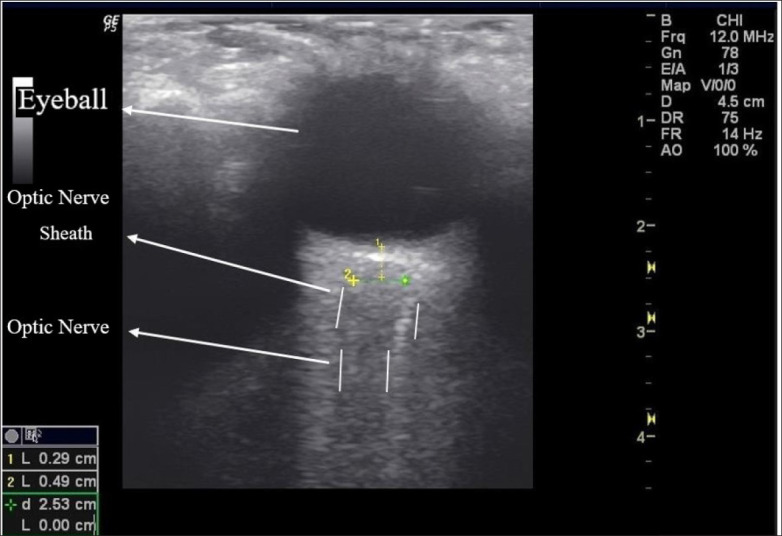

Background: The Trendelenburg position and pneumoperitoneum may cause cerebral edema and increased intracranial pressure. Non-invasive measurement of the diameter of the optic nerve sheath by ultrasonography can provide early recognition of intracranial pressure.

Objective: Evaluate the optic nerve sheath diameter (ONSD) changes in patients who undergo laparoscopic surgery in the Trendelenburg position and make indirect conclusions about changes in intracranial pressure.

Patients and methods: Patients aged 18-75 years who underwent laparoscopic surgery in the Trendelenburg position under general anesthesia were included in our study. The ONSD was measured four times: Immediately after tracheal intubation, in the neutral position (baseline value) (T0), 10 minutes after pneumoperitoneum and Trendelenburg position (T1), 60 minutes after pneumoperitoneum and Trendelenburg position (T2), and 10 minutes after the pneumoperitoneum is terminated and placed in the neutral position (T3).

Main outcome measures: Compare ONSD measured by ultrasonography at different times of surgery.